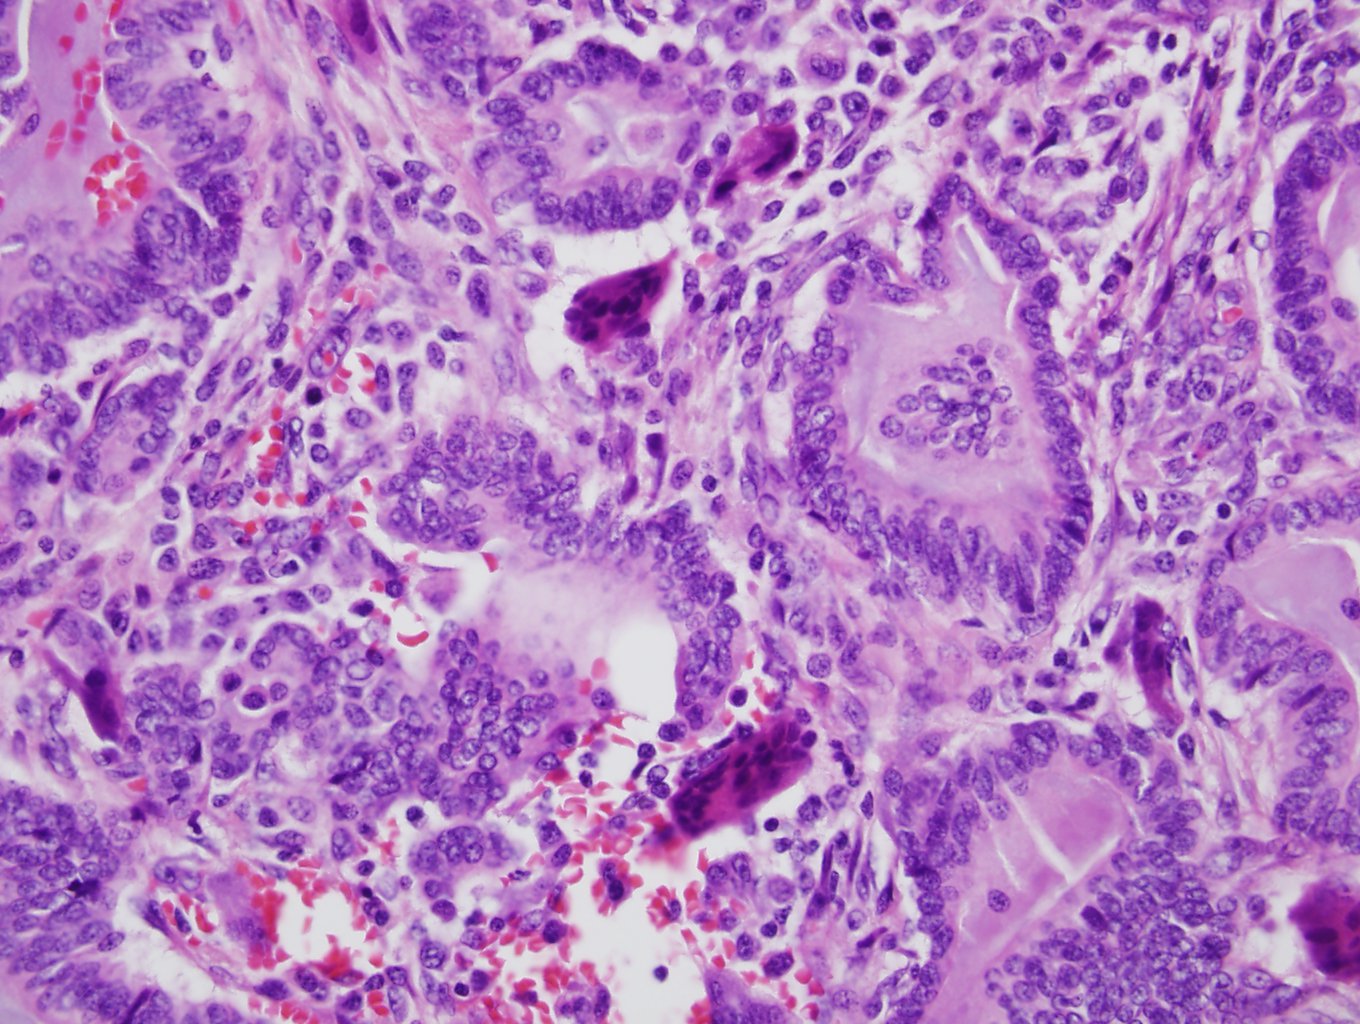

The answer is “C”, Invasive mammary carcinoma with osteoclast-like giant cells

The sections show infiltrating ductal cells that are forming glandular pattern. Stromal hemorrhage with hemosiderin and lymphocytes are seen. Multinucleated giant cells are seen in intervening stroma and in the glandular lumens. The mechanism by which osteoclast-like giant cells are formed in breast carcinoma is not known. It has been postulated that one or more substances produced by the neoplastic cells induces the formation and the same process may be responsible for the angiogenesis and hemorrhage. These giant cells are positive for CD68 and negative for vascular markers, suggesting these cells are similar to histiocytic or osteoclasts of bone. The carcinoma cells are similar to ductal carcinoma, tends to be luminal type (hormone receptor positive). Although number of reported cases is limited, these tumors tend to show better prognosis with relatively low metastasis or recurrence rate.